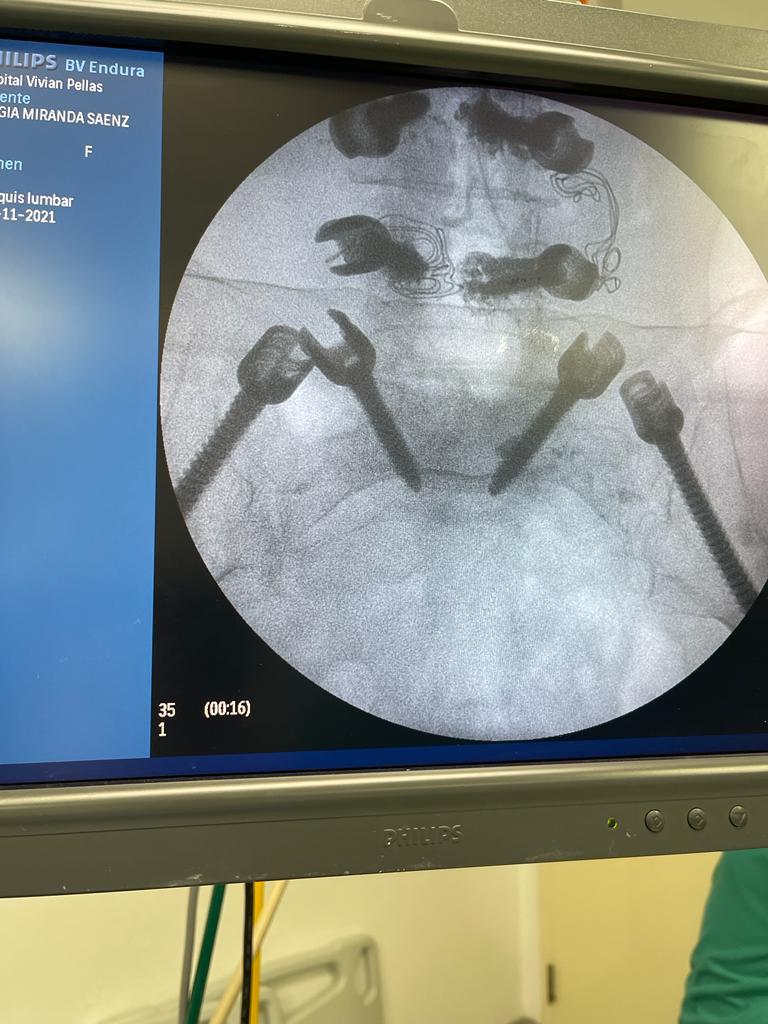

4. Fusión Vertebral (Lumbosacra o Cervical)

¿Qué es?

Cirugía que une dos o más vértebras para estabilizar la columna y aliviar el dolor.

Fusión Vertebral (Cervical o Lumbosacra)

Es un procedimiento quirúrgico que busca estabilizar la columna vertebral uniendo de forma permanente dos o más vértebras. Se utilizan tornillos, barras y, en ocasiones, una caja intersomática con injerto óseo, para que las vértebras se fusionen en una sola unidad sólida.